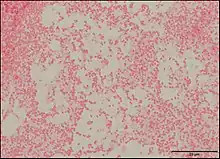

Pseudescherichia vulneris is a Gram-negative bacterial species. P. vulneris is a fermentative, oxidase-negative, motile rod, which holds characteristics of the family Enterobacteraceae. This bacterium can colonize in the respiratory tract, genital tract, stool, and urinary tract. However, P. vulneris is most often associated with wounds and has been known to colonize open wounds of both humans and animals. This association gave the bacterium its species name, vulneris, which is Latin for wound. It has also been infrequently reported in cases of meningitis. It was identified as Escherichia vulneris in 1982 with a 2017 genomic analysis of its original genus resulting in the creation of its new genus Pseudescherichia.[1][2]

P. vulneris has a rod-like (bacilli) shape, and it achieves motility using peritrichous flagella (covering the whole body of the bacteria). P. vulneris is facultatively anaerobic, and is not spore-forming. Optimal growth occurs at 35-37 °C, and it can colonize on a simple nutrient medium. Colonies are generally smooth and low convex with shiny surfaces.[3]